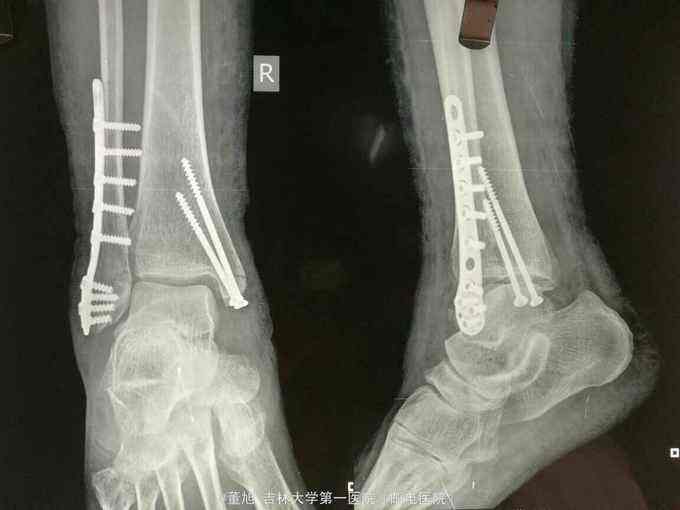

不是很直观吧?举个例子,醉驾致人小腿下三分之一处撞骨折,需要打钢板,属不属于重伤?

车祸双踝骨折内固定一般不属于重伤

参照《人体损伤致残程度分级》,一般会被评定为十级伤残。我们可以申请法院、交警大队、甚至可以自己委托鉴定机构进行鉴定,这也是作为民事赔偿的依据。

但此处的轻、重伤评定不参照这个文件,而是参照同样两高三部下发的《人体损伤程度鉴定标准》,对重伤、轻伤进行鉴定,一般是报警后,由公安局指定鉴定,这才是认定是否构成刑事犯罪的标准。而上文说的小腿下三分之一处撞骨折,根据《人体损伤程度鉴定标准》

5.9.3,a)四肢任一大关节功能丧失25%以上。

属于轻伤一级,不属于重伤。